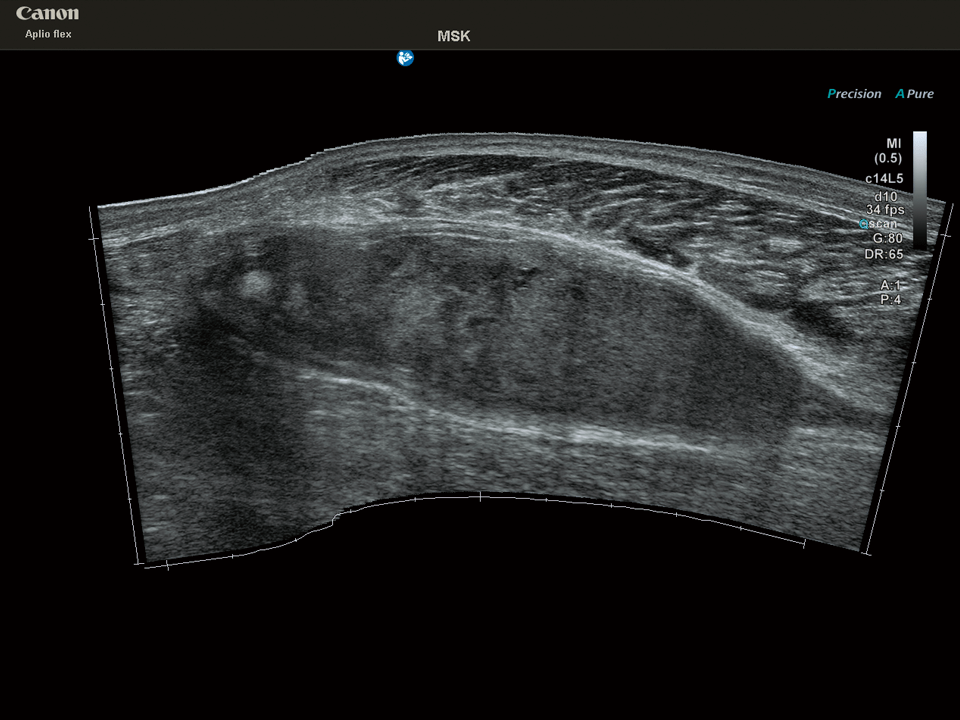

Panoramic View*

プローブを体表に沿ってスキャンさせることで、画像をプローブの走査方向につなぎ合わせてプローブの視野幅を超える画像を表示することが可能です。